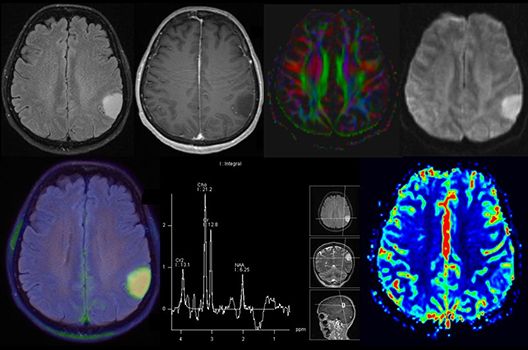

Die Hybridbildgebung mittels PET/MRT spielt insbesondere in der onkologischen Bildgebung eine wichtige Rolle. Eine mögliche Fragestellung ist die Unterscheidung zwischen einem Tumorrezidiv oder therapeutisch assoziierten Veränderungen insbesondere dann, wenn diese Frage mittels MRT alleine nicht beantwortet werden kann.

Die bildgebende Diagnostik und Verlaufsbeurteilung von Tumoren des Nervensystems ist einer der klinischen und Forschungsschwerpunkte unserer Abteilung. Eine besondere Bedeutung kommt der Hybrid-Bildgebung zu. Das Universitätsklinikum verfügt über einen integrierten Ganzkörper-PET/MRT-Scanner, der die Vorteile der MRT-Bildgebung und der Positronenemissionstherapie (PET) vereinigt. Aufgrund der langjährigen klinischen Arbeit und Forschungstätigkeit mit diesem Gerät hat die Neuroradiologie Tübingen maßgeblich zur Etablierung dieses Verfahrens beigetragen. Auch weiterhin forschen wir intensiv an neuen Methoden zur frühen Einordnung von Tumoren und insbesondere Tumorrezidiven, die mit anderen Methoden häufig nicht erfasst werden können.